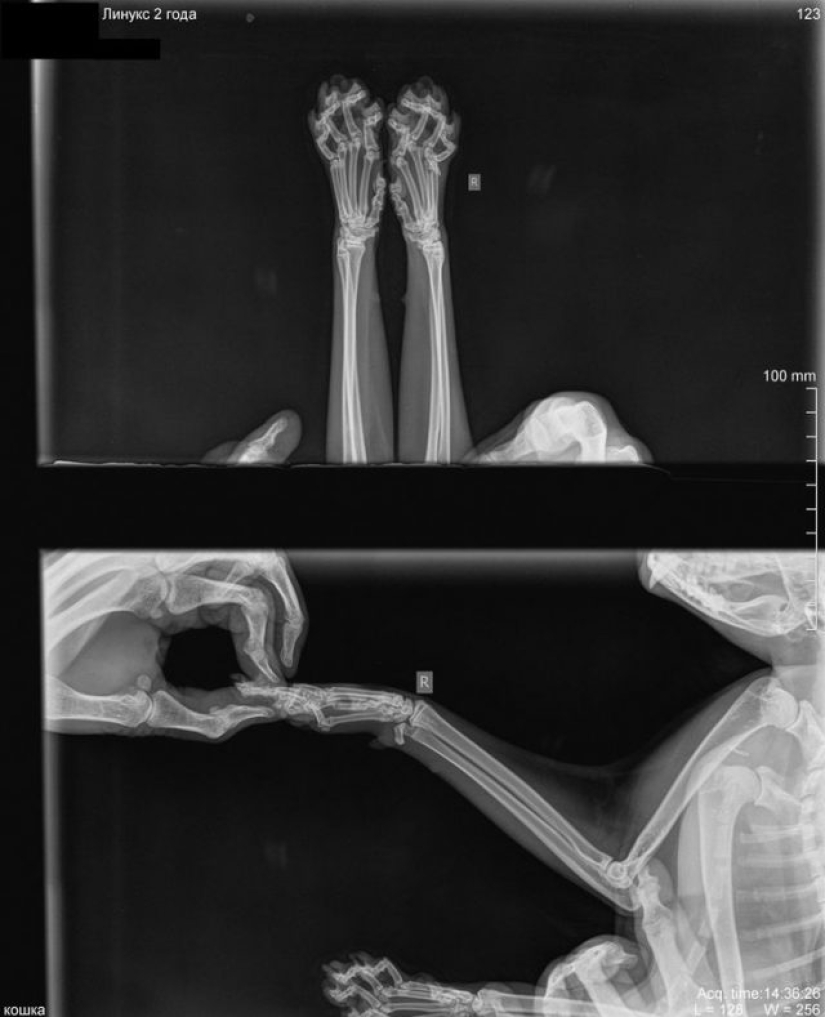

9. Así es como se ve un gato translúcido: